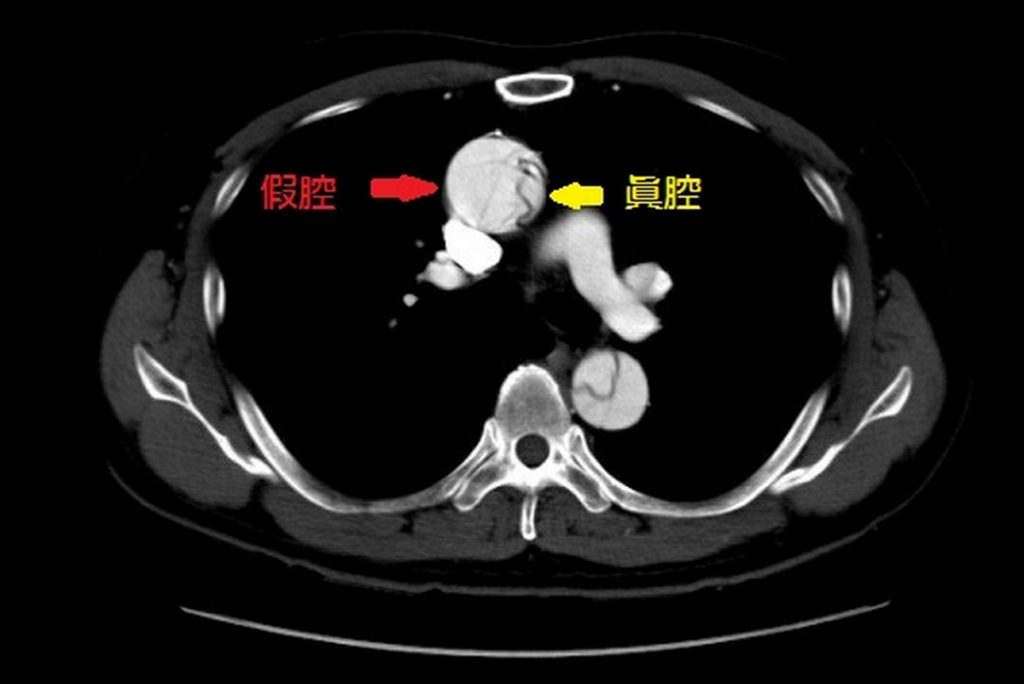

諶大中說,主動脈壁由內、中、外三層結締組織構成,正常狀態下主動脈內壁富有彈性,可一旦因高壓使動脈內層破裂產生縫隙時,血流會將主動脈撕裂成「假腔」與「真腔」兩個腔室,形成「主動脈剝離」。